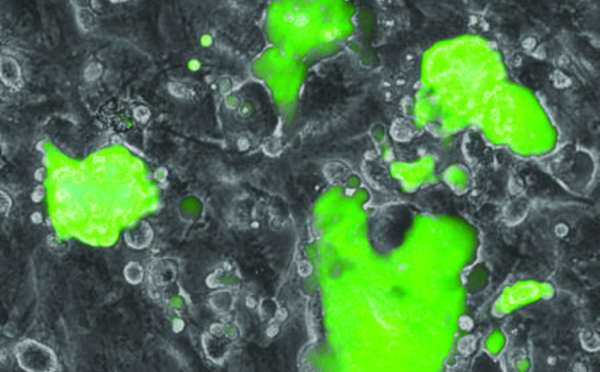

Reprogramación exprés de células adultas en células pluripotentes inducidas - 16/12/2013

Un grupo de investigadores del Centro de Regulación Genómica de Barcelona han descubierto un mecanismo por el cual la reprogramación de células adultas en células madre pluripotentes inducidas es mucho más rápida y eficiente. El descubrimiento, que el próximo domingo adelanta la prestigiosa revista 'Nature', permite que la reprogramación de células pase de un par de semanas a pocos días y aporta nueva información sobre el proceso de reprogramación de células iPS y sus potenciales aplicaciones médicas.